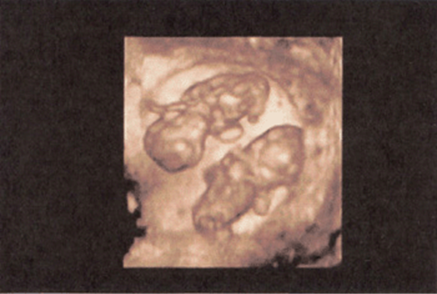

FIGURE 8–6. Three-dimensional image of twins at 11-weeks’ gestation. (Courtesy of Philips Healthcare.)